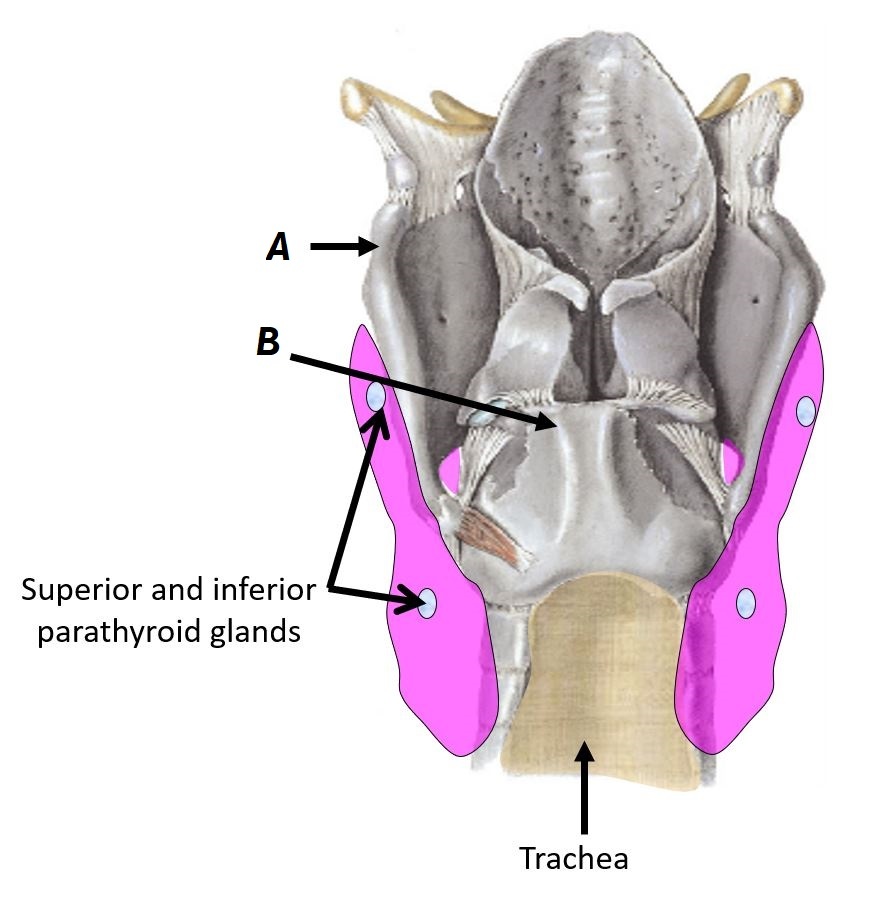

Name structures A and B

A - Thyroid cartilage

B - Cricoid cartilage

Name structures A and B

A - Parathyroid glands

B - Trachea

Name structures A and B

A - Thyroid cartilage

B - Cricoid cartilage